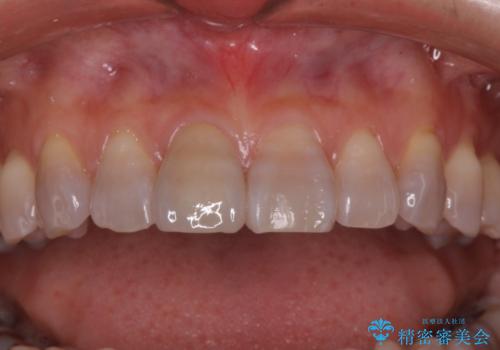

転んで前歯が折れた 色合いの難しい歯のセラミック修復

テトラサイクリン歯といって縞模様の強い歯の色調再現を行いました。

- 16.5万円(内訳:仮歯1万円、ジルコニアクラウン(スペシャル)14万円)費用は治療当時の料金となります

まず保険治療でコンポジットレジン修復を行い、神経の状態を確認した後、クラウンによる修復を行いました。

将来神経が失活する可能性もありますので経過観察する必要があります。